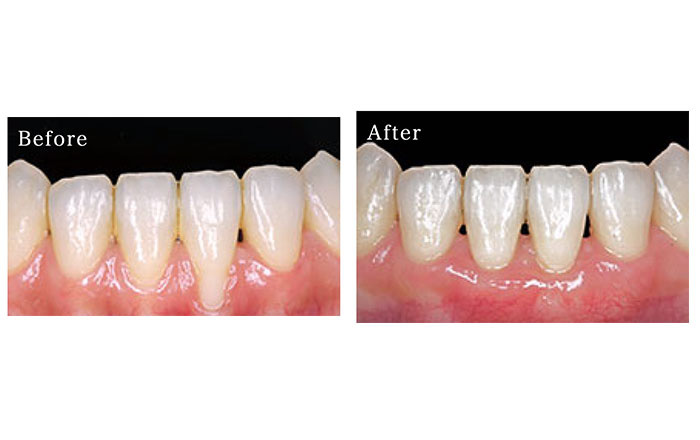

7.歯の根っこが露出した部分を再生する、結合組織移植術(CTG)

結合組織移植術(CTG)は、歯ぐきが下がり、歯の根っこが露出してしまった部分の歯ぐきを再生する目的で行われます。

前歯部分などの歯ぐきや、骨の薄い箇所で行われることが多いです。

手術部位を開き、6の遊離歯肉移植術と同様に、上顎の歯ぐきから上皮と言われる組織のついた歯ぐきを採取し、移植したい部分に移植します。

1)結合組織移植術(CTG)のメリット

・採取した歯ぐきに血液の供給が十分であれば、手術の成功率が高い

・歯ぐきの色が異なる審美性の問題が、遊離歯肉移植術よりも気にならない

2)結合組織移植術(CTG)のデメリット

・手術部位が2箇所になる(移植する部位と歯ぐきを取ってくる部位)

・上顎の歯ぐきが薄いとできない場合がある